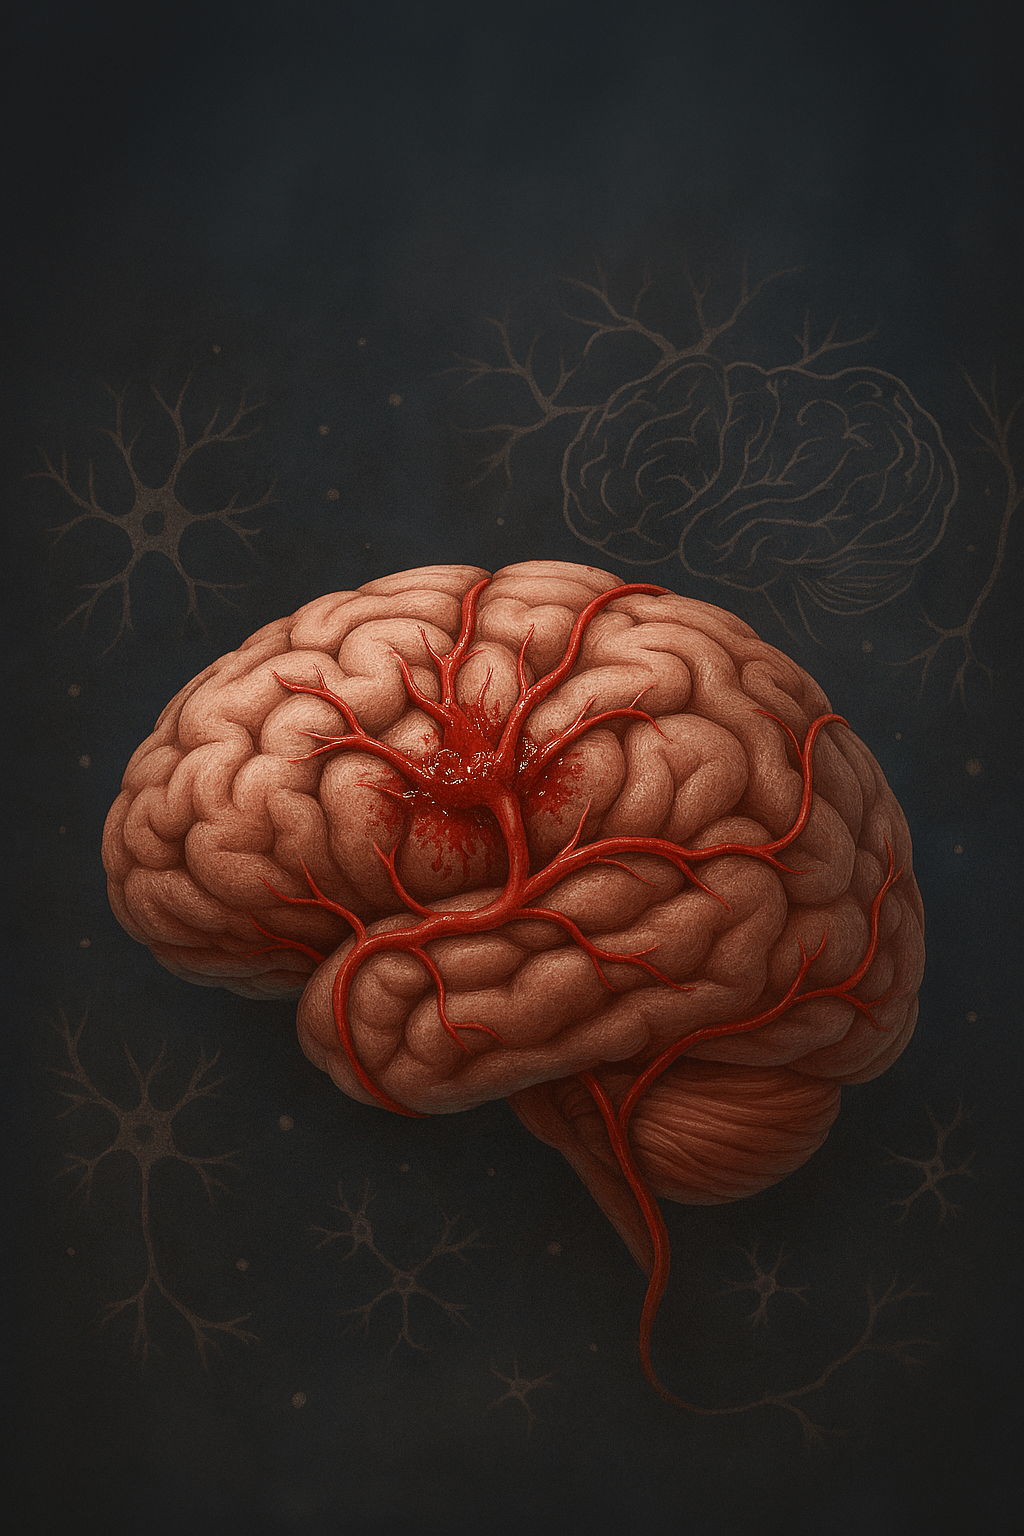

Now, obviously, the neurological deficits won’t come unless you actually experience the stroke…so let’s discuss how the stroke actually forms, progresses, and presents itself. There are two primary types of a stroke: an ischemic stroke, and a hemorrhagic stroke, both which involve blood, and obviously, the brain. Now, an ischemic stroke likely is the one most people are referring to when they say ‘stroke,’ as they are much more common than hemorrhagic strokes. In this case, there is a clot or blockage in the affected artery, causing the backup of blood within the brain. The flow of blood doesn’t completely ‘stop’, because there are drainage systems within the brain…however, when it comes to the area of the brain directly affected by that specific branch of the artery, perfusion is lost, hence the lack of coordination or cohesion often observed in these individuals. In a hemorrhagic stroke, a blood vessel bursts…totally bursts. Yes…it bursts. It can either burst within the neuron, or in the subarachnoid space. So, we have a basic understanding of how strokes occur (both types), and intuitively, a disruption of blood is bad for your brain…but how, or for what reason.

To the left is an MRI Image of a patient suffering a stroke, around what seems like the Left Frontal Lobe. As you can see, the lack of blood flow (Ischemic) creates a whitish, obviously deficient appearance in the brain